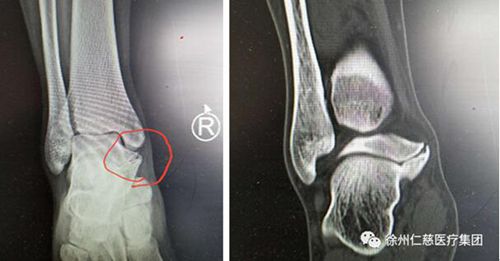

在求治多家醫(yī)院后,本周一上午小朱來(lái)到仁慈醫(yī)院足踝外科專(zhuān)家門(mén)診,當(dāng)時(shí)正是業(yè)務(wù)院長(zhǎng)石榮劍坐診,經(jīng)過(guò)詢(xún)問(wèn)病史、體檢和X光、CT三維重建,石院長(zhǎng)發(fā)現(xiàn)患者腳里跟骨和距骨間長(zhǎng)出來(lái)了一個(gè)像橋一樣的高密度影,最終診斷是少見(jiàn)的跟距骨橋。

跟距骨橋分先天性和繼發(fā)性?xún)煞N,繼發(fā)性跟距骨橋患者一般都有明確的足扭傷病史,患者的主要臨床表現(xiàn)為跟距關(guān)節(jié)內(nèi)側(cè)突起,伴局部壓痛明顯,跑跳時(shí)疼痛加重,中、后足活動(dòng)受限。